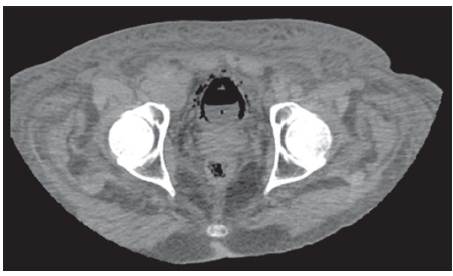

Se recibe reporte de patología, el cual evidencia tumor neuroendocrino tipo células de Merckel; entonces se valora por Oncología, donde indican inicio de quimioterapia ambulatoria, una vez se dé el egreso hospitalario. Una semana después el paciente presenta hematuria franca y oliguria; en estudios de laboratorios evidencian uroanálisis con hematuria, proteinuria en rango nefrótico y sedimento activo, con función renal dentro de parámetros de normalidad. Dados los nuevos hallazgos clínicos y el antecedente de diabetes, se decide solicitar estudios adicionales, descartando por oftalmología retinopatía diabética; adicionalmente el equipo de Nefrología descarta síndrome nefrótico, al evidenciar orina de 0,3 g en 24 horas, hipoalbuminemia y perfil lipídico normal; así mismo la morfología globular se encontraba en el 60% de hematíes eumorfos, descartando glomerulopatías. Investigando el origen de la hematuria, se complementa con estudios anatómicos; en efecto, se inicia con ecografía de vías urinarias que reportan buena diferenciación cortico-medular con riñones conservados de tamaño; posteriormente se solicita UROTAC para observar el tracto urinario bajo, evidenciándose engrosamiento de la pared vesical, gas perivesical como se observa en las imágenes 1, 2 y 3, y con conglomerados ganglionares retroperitoneales, hallazgos compatibles con cistitis enfisematosa.

Dado el hallazgo anterior se solicita urocultivo y baciloscopia en orina para determinar la etiología, y adicionalmente se pide valoración por urología, descartando indicación de manejo quirúrgico. Las baciloscopias seriadas de orina son negativas y en el urocultivo se aisla E. coli patrón BLEE; se indicó continuar manejo antibiótico con ertapenem por 14 días y seguir con sonda vesical; posteriormente cesa hematuria macroscópica y aumento el gasto urinario. En relación con conglomerados ganglionares descritos, se planteó posible compromiso tumoral para posterior seguimiento de forma ambulatoria con servicio de oncología. Ver cuadro paraclínicos.

Para el diagnóstico de la CE y para descartar diagnósticos diferenciales como fístula vésicocólica, abscesos intraabdominales, neoplasias adyacentes y pielonefritis enfisematosa, se hace necesario el uso de métodos imagenológicos como la radiografía abdominal convencional simple, la ecografía abdominal y la tomografía computarizada, donde pueda ser evidenciado el gas en la vejiga, el engrosamiento de las paredes vesicales9.

El caso aquí reportado se correlaciona con lo encontrado en la literatura desde el punto de vista del aislamiento microbiológico que corresponde a una Escherichia coli, aunque el nuestro es una E. Coli con patrón de resistencia a betalactamasas de espectro extendido (BLEE), probablemente por las complicaciones anotadas, como la hospitalización previa para el manejo posoperatorio del colgajo de piel y el uso de antibióticos en dicha hospitalización. También, se correlaciona con la literatura en la presentación del cuadro clínico, el antecedente de diabetes como el factor de riesgo más asociado, y en el abordaje diagnóstico, en el cual se pudo documentar el aire perivesical por medio del UROTAC, que es el examen con mayor sensibilidad y especificidad para el diagnóstico de esta patología.